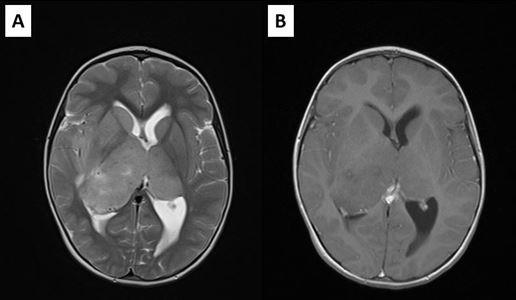

We present a case of a 5-year-old girl admitted with signs of raised Intracranial Pressure (headache, vomiting and lethargy) (ICP) and left sided hemiparesis that lasted for two weeks. Systemic examination was normal and neurological examination revealed upward gaze palsy, mild left sided hemiparesis, and chronic papilledema with 2.5D on the left, and 3.5D on the right eye. Brain CT scan showed large isodense mass involving bithalamic region with right sided predominance and ventricular enlargement. There was no contrast enhancement (Figure 1). Brain MRI showed huge bithalamic lesion, with some right sided predominance. It was uniformly isointense on T1 weighted and, hyperintense on T2 and FLAIR weighted images, with no contrast enhancement. Lateral ventricles were enlarged (Figure 2). After VP shunt placement and corticosteroid therapy symptoms resolved. In the second surgery patient was operated through the right, nondominant parietal lobulus since tumor mass was larger in the right thalamus, filling the body of the right lateral ventricle with significant lateral and posterior extension. During the operation body of the right ventricle was entered, and intraventricular tumor mass was removed. Tumor was without clear border to right thalamus. Most of the right sided mass was removed. Postoperative course went uneventful.

Figure 1: Initial brain CT showing the bithalamic tumor: (A) native study; (B) contrast enhanced study.